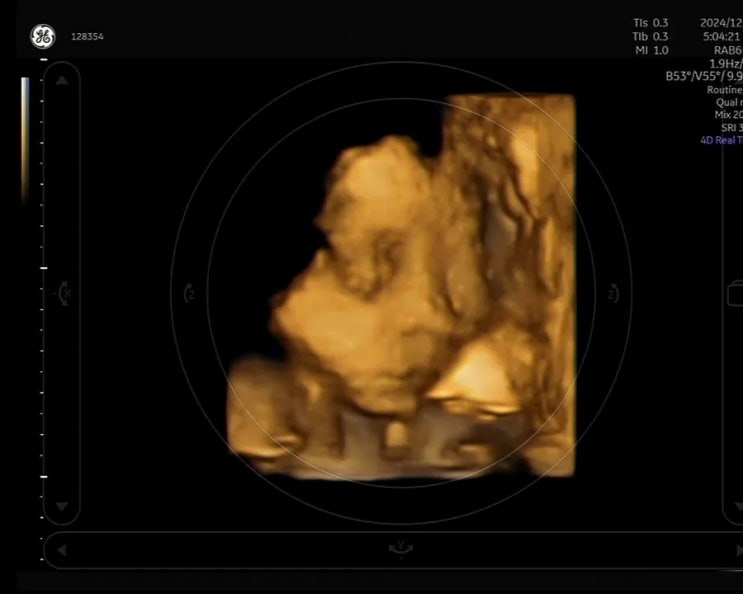

튼튼이. 도하가 태어났어요! 전주미르피아 임당산모 신생아 우량아

유도분만을 하려고했으나 진통 13시간.. 튼튼이는 골반안으로 들어오지못하고 (권원장님이 내 골반 좋다했...